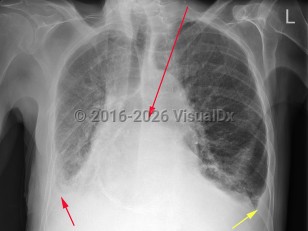

Congestive heart failureCongestive heart failure

Acute respiratory distress syndromeAcute respiratory distress syndrome